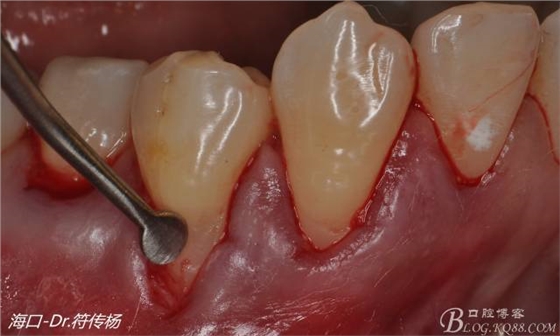

然后使用下頜開隧刀剝離牙齦

最后使用牙齦乳頭分離器分離牙齦乳頭

接著從腭部上皮下取出結(jié)締組織

確定取出結(jié)締組織長(zhǎng)度是否適當(dāng)